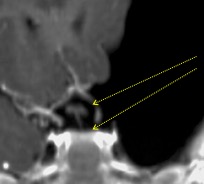

quatrième ventricule exclu

la reperméation de l’aqueduc est aisée en cas d’hydrocéphalie, car elle peut être réalisée du haut vers le bas. il ne faut pas dilater le ballon en raison d’un risque de troubles oculomoteurs.

la reperméation de l’aqueduc est plus difficile quand il s’agit d’un V4 exclu avec des ventricules sus-jacents bien drainés. il est préférable de laisser un cathéter en place comme stent pour éviter la re-sténose.